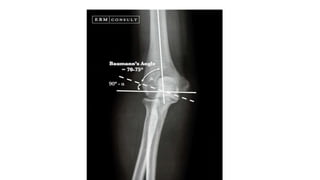

3. Baumen’s angle :

 In AP X-ray of the elbow a line drawn along the long axis of the

humeral shaft & a line through the coronal axis of the capitellar

physis.

 Normally the angle is less than 80 degrees.

 If the distal fragment is tilted varus, the increased angle is readily

detected.

3. Baumen’s angle:  In AP X-ray of the elbow a line drawn along the long axis of the humeral shaft & a line through the coronal axis of the capitellar physis.  Normally the angle is less than 80 degrees.  If the distal fragment is tilted varus, the increased angle is readily detected.